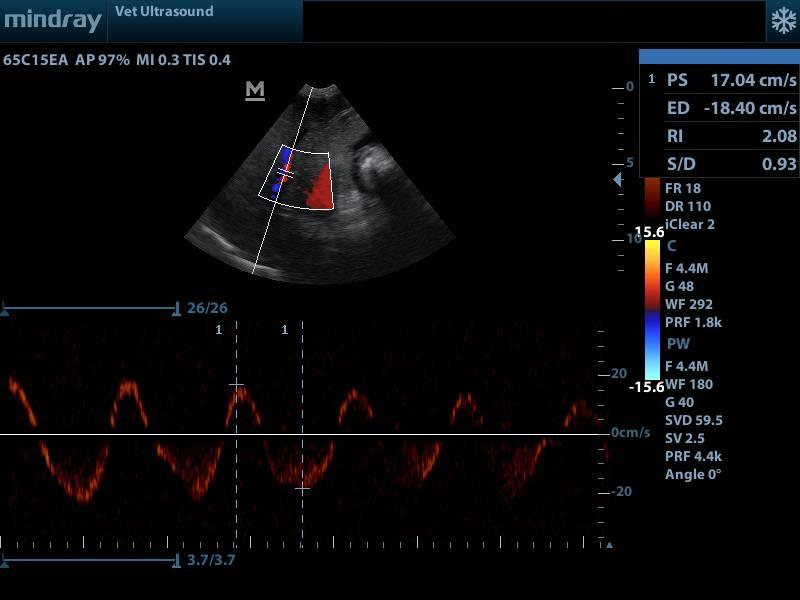

Στον έλεγχο της ροής της ηπατικής φλέβας ελέγχθηκε διαφορετική κυματομορφή ( to and fro)

από την φυσιολογική (triphasic).